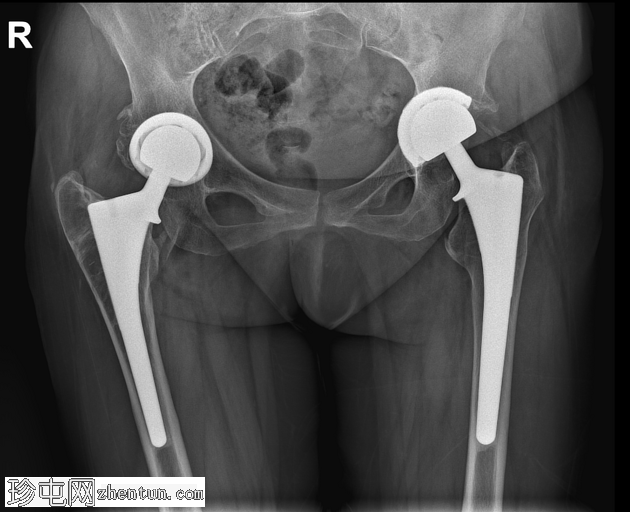

X线片

正位片

双侧全髋关节置换术假体完整,无松动迹象。

左侧股骨大转子下区外侧皮质中断,侧位片显示最佳,提示假体周围骨折。